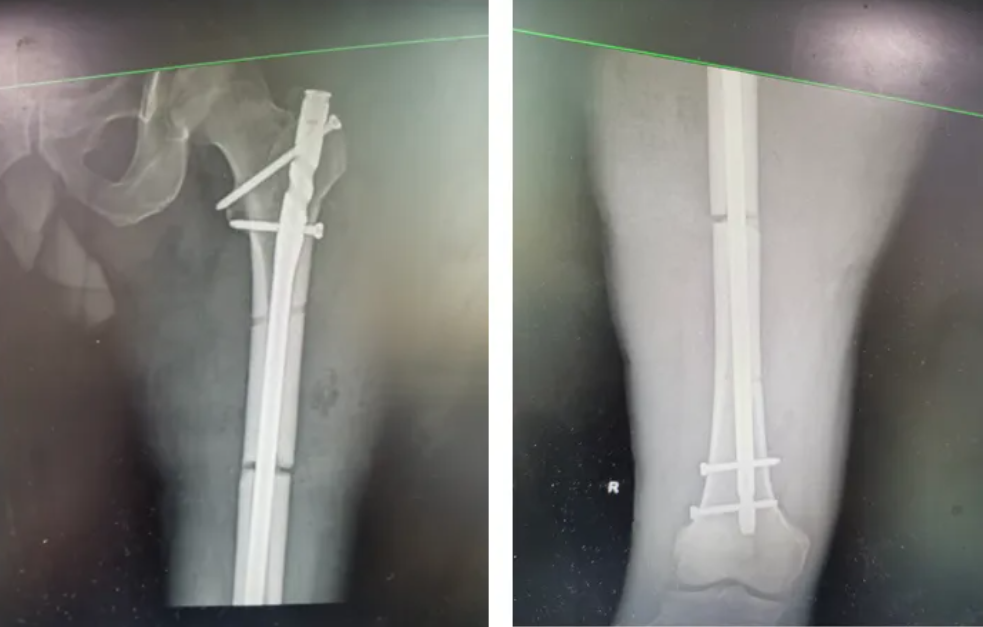

一周后,在椎管内麻醉下行右股骨干骨折闭合复位髓内钉内固定术,术后医护团队给予全方位的指导,以促进骨骼愈合,恢复肌肉力量,预防并发症为主。

钢筋穿透伤是严重的多发性创伤,按照受累部位涉及多个科室,病情复杂,存在很多不确定性,而股骨干骨折是指大腿骨的中间部分发生断裂。这种骨折通常由高能量损伤引起,如车祸、高处坠落或严重的撞击。股骨干骨折的治疗可能包括手术固定或非手术治疗,具体取决于骨折的类型、位置和患者的整体健康状况。在治疗过程中,患者可能需要使用牵引或支具来稳定骨折部位,直至愈合。康复过程可能需要物理治疗来恢复腿部的力量和功能。